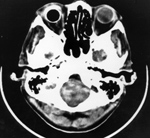

| Pen in orbit |

Pen in orbit |

| 10 year-old boy running with a ballpoint pen in his mouth. He fell and jammed the pen into the soft tissues of his face, entering the mouth under his upper lip. He recovered fully. (Courtesy George Barnes, MD). From Hunter, 1994 |